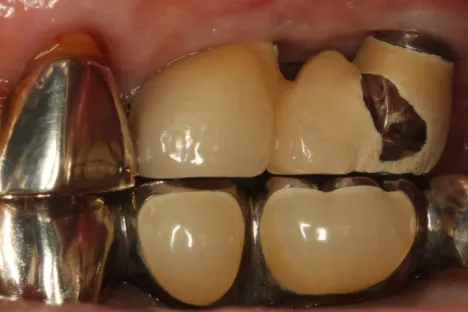

Dr.Tachikawa_Fig.2

Fig. 2. Pre-operative intraoral photograph. The superstructure was removed, a healing abutment was placed at 25, and a cover screw was placed at 26.